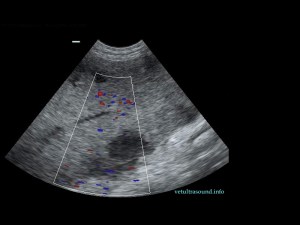

Ευρήματα: Η κεφαλή του σπλήνα βρέθηκε μετατοπισμένη ( στραμένη προς τα οπίσθια άκρα) με υποκαψικές περιοχές υποηχογένειας, χωρίς αιμάτωση (pic 1,2,3). Το τμήμα αυτό του σπλήνα ήταν διογκωμένο σε σχέση με το υπόλοιπο όργανο και το μεσεντέριο λίπος που το περιέβαλε ήταν έντονα υπερηχογενές. Στο συγκεκριμένο σημείο του σπλήνα τα μεγάλα αγγεία δεν είχαν ροή αίματος κατά τον έλεγχο με έγχρωμο Doppler (pic3). Αντίθετα το σώμα και η ουρά του οργάνου είχαν φυσιολογική αιμάτωση και μέγεθος (pic 4,5).